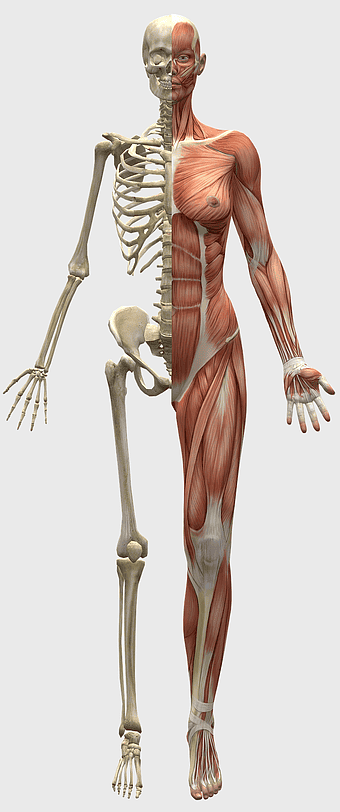

Breast cancer, musculoskeletal system, human anatomy, health care, skeletal muscle structure, medical illustration, body composition analysis -

Human skeleton, human body anatomy, standing skeleton, bone structure, skeletal system, medical illustration, human anatomy study -

human anatomy diagram, muscular system illustration, human body muscles, fitness anatomy chart, skeletal muscle structure, human physiology study, muscle group analysis